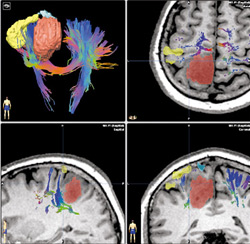

Pikeville Medical Center was the first and only hospital in the region, and is among only a select few hospital’s in the nation to offer the Brainlab system. With the use of this guided cranial navigation system Dr. Mayer helps patients recover from tumors and other brain related injuries more efficiently.

The Brainlab system also allows the neurosurgeon to make an accurate and noninvasive assessment of a patient’s brain injury and the procedure, before an operation takes place. Once in surgery, the neurosurgeon takes comfort in knowing that he/she is now able, due to Brainlab technology, to perform a less invasive procedure. Before Brainlab more aggressive surgical procedures were used, which at times could cause new neurological problems in patients such as: weakness on the opposite side of the body or difficulty speaking.

With Brainlab, surgeons can see the tumor in 3D. They can look at vital structures around the tumor and find that small, safe corridor through the door. This system allows us to plan our path, our journey into the brain and sneak the tumor out.